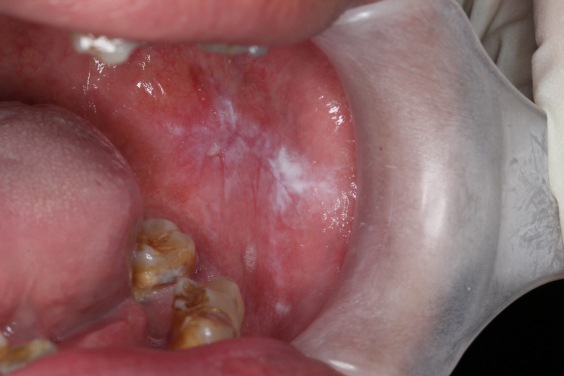

Oral cancer often develops from white patches clinically known as oral leukoplakia (OL) and oral lichenoid mucositis (OLM). These white patches may appear long before a diagnosis of oral cancer, and their early detection and continuous monitoring are crucial to prevent the development of cancer. However, it is sometimes challenging to predict which OL/OLM lesions will develop into oral cancers as the global risk rates of progression from OL/OLM to cancer vary from 0.4 to 40.8%.